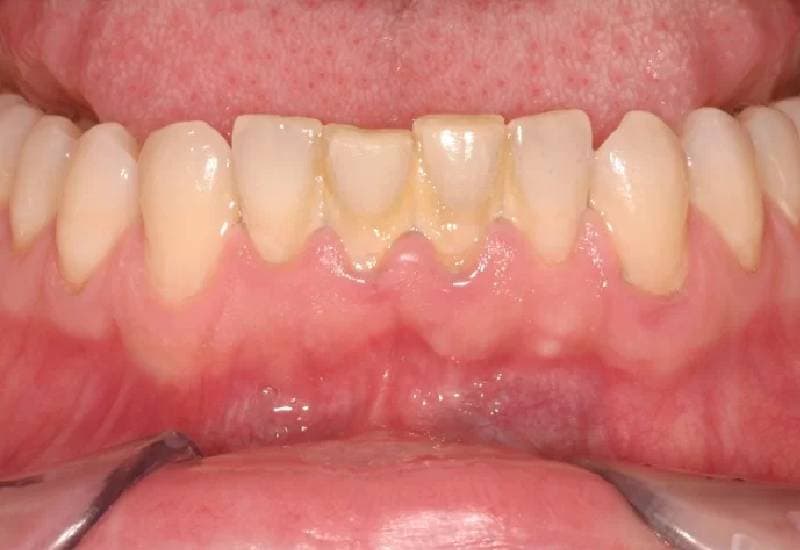

– Nướu tụt, lộ chân răng

1.3. Ảnh hưởng do viêm nướu

Là một trong những bệnh lý răng miệng phổ biến, nhưng viêm nướu răng thường không được quan tâm đúng cách. Rất nhiều người thường lơ là, phớt lờ bệnh và nghĩ tình trạng này sẽ tự khỏi, chỉ đến khi thấy tình trạng viêm nướu nghiêm trọng hơn mới đi mua thuốc hoặc đi khám. Trong khi đó, các bác sĩ Răng Hàm Mặt của TCI khuyến cáo: Nếu không được điều trị kịp thời, người bệnh viêm nướu có thể gặp biến chứng viêm nha chu, gây tổn thương nghiêm trọng đến mô nướu và xương hàm, thậm chí dẫn đến mất răng.

Với viêm nướu răng, các bác sĩ cũng cho biết, việc điều trị bệnh ngay từ sớm sẽ giúp người bệnh tiết kiệm thời gian điều trị với những phương pháp đơn giản. Khi càng để lâu, mức độ ảnh hưởng và biến chứng của viêm nướu càng lớn, điều trị cũng khó khăn và tốn kém hơn.

Viêm nướu gây khó khăn trong ăn uống và nhiều nguy cơ bệnh răng miệng